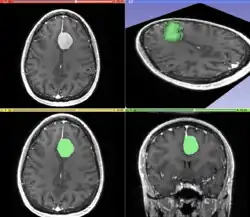

Image and sound processing

Information can take the form of images, sound, video or other multimedia. Bits of information can be streamed via signals. Its processing is the central notion of informatics, the European view on computing, which studies information processing algorithms independently of the type of information carrier – whether it is electrical, mechanical or biological. This field plays important role in information theory, telecommunications, information engineering and has applications in medical image computing and speech synthesis, among others. What is the lower bound on the complexity of fast Fourier transform algorithms? is one of the unsolved problems in theoretical computer science.

| FFT algorithms | Image processing | Speech recognition | Data compression | Medical image computing | Speech synthesis |